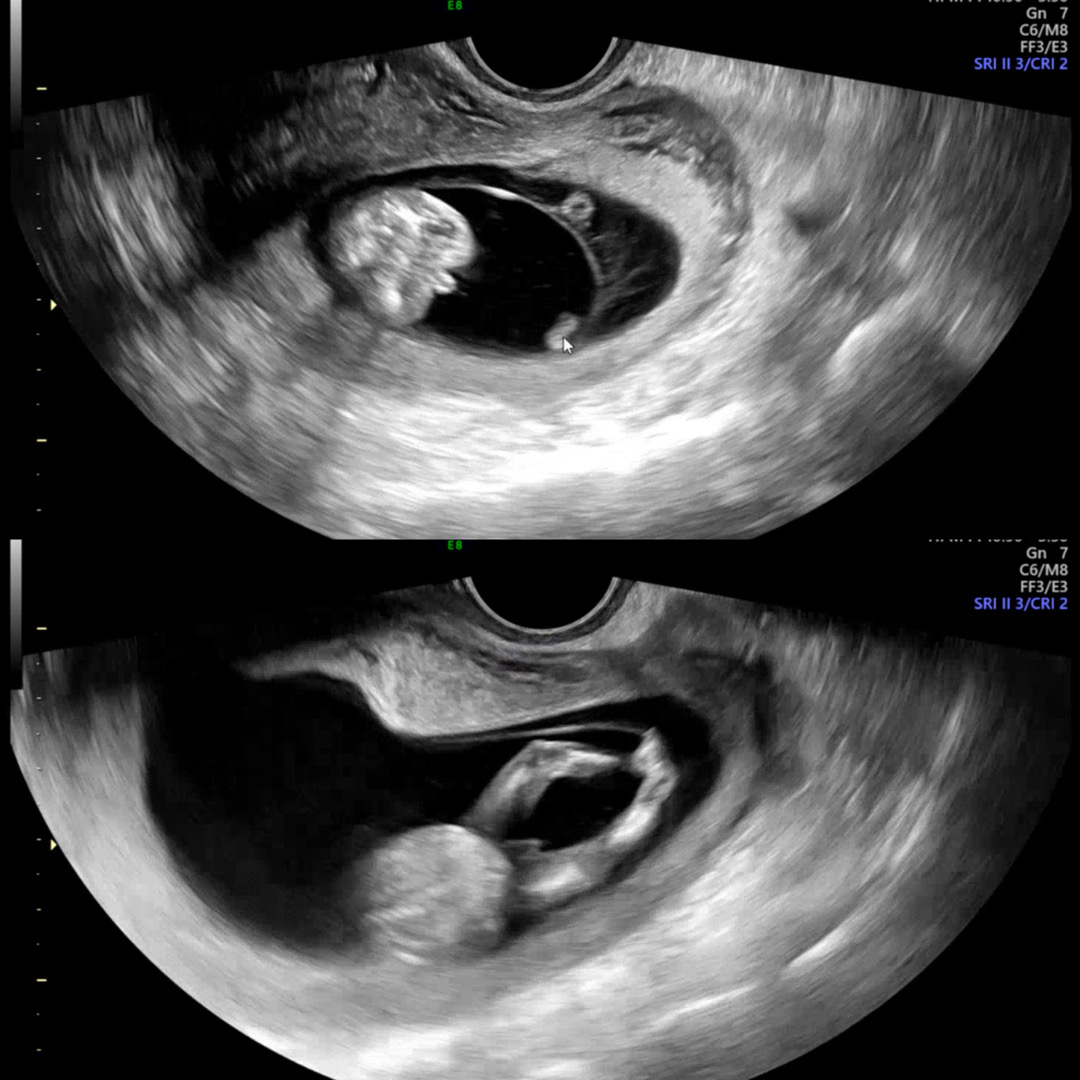

12주초음파 같이 봐주세요!

12주5일차로 오늘 첫 기형아검사 하구 왔어요 😖 이 사진 아들일까요 딸일까요? 첫번째 사진은 엉덩이사이에요ㅠㅋㅋ 꽁꽁 감추고 있다가 보여줬는데 16주차에 반전일수도 있다고는 하는데..너무 궁금하네요ㅠ

12주차에는 아들도 딸도 튀어나와보여서 알 수 없고, 각도법으로 추정만 가능해요 ㅠ